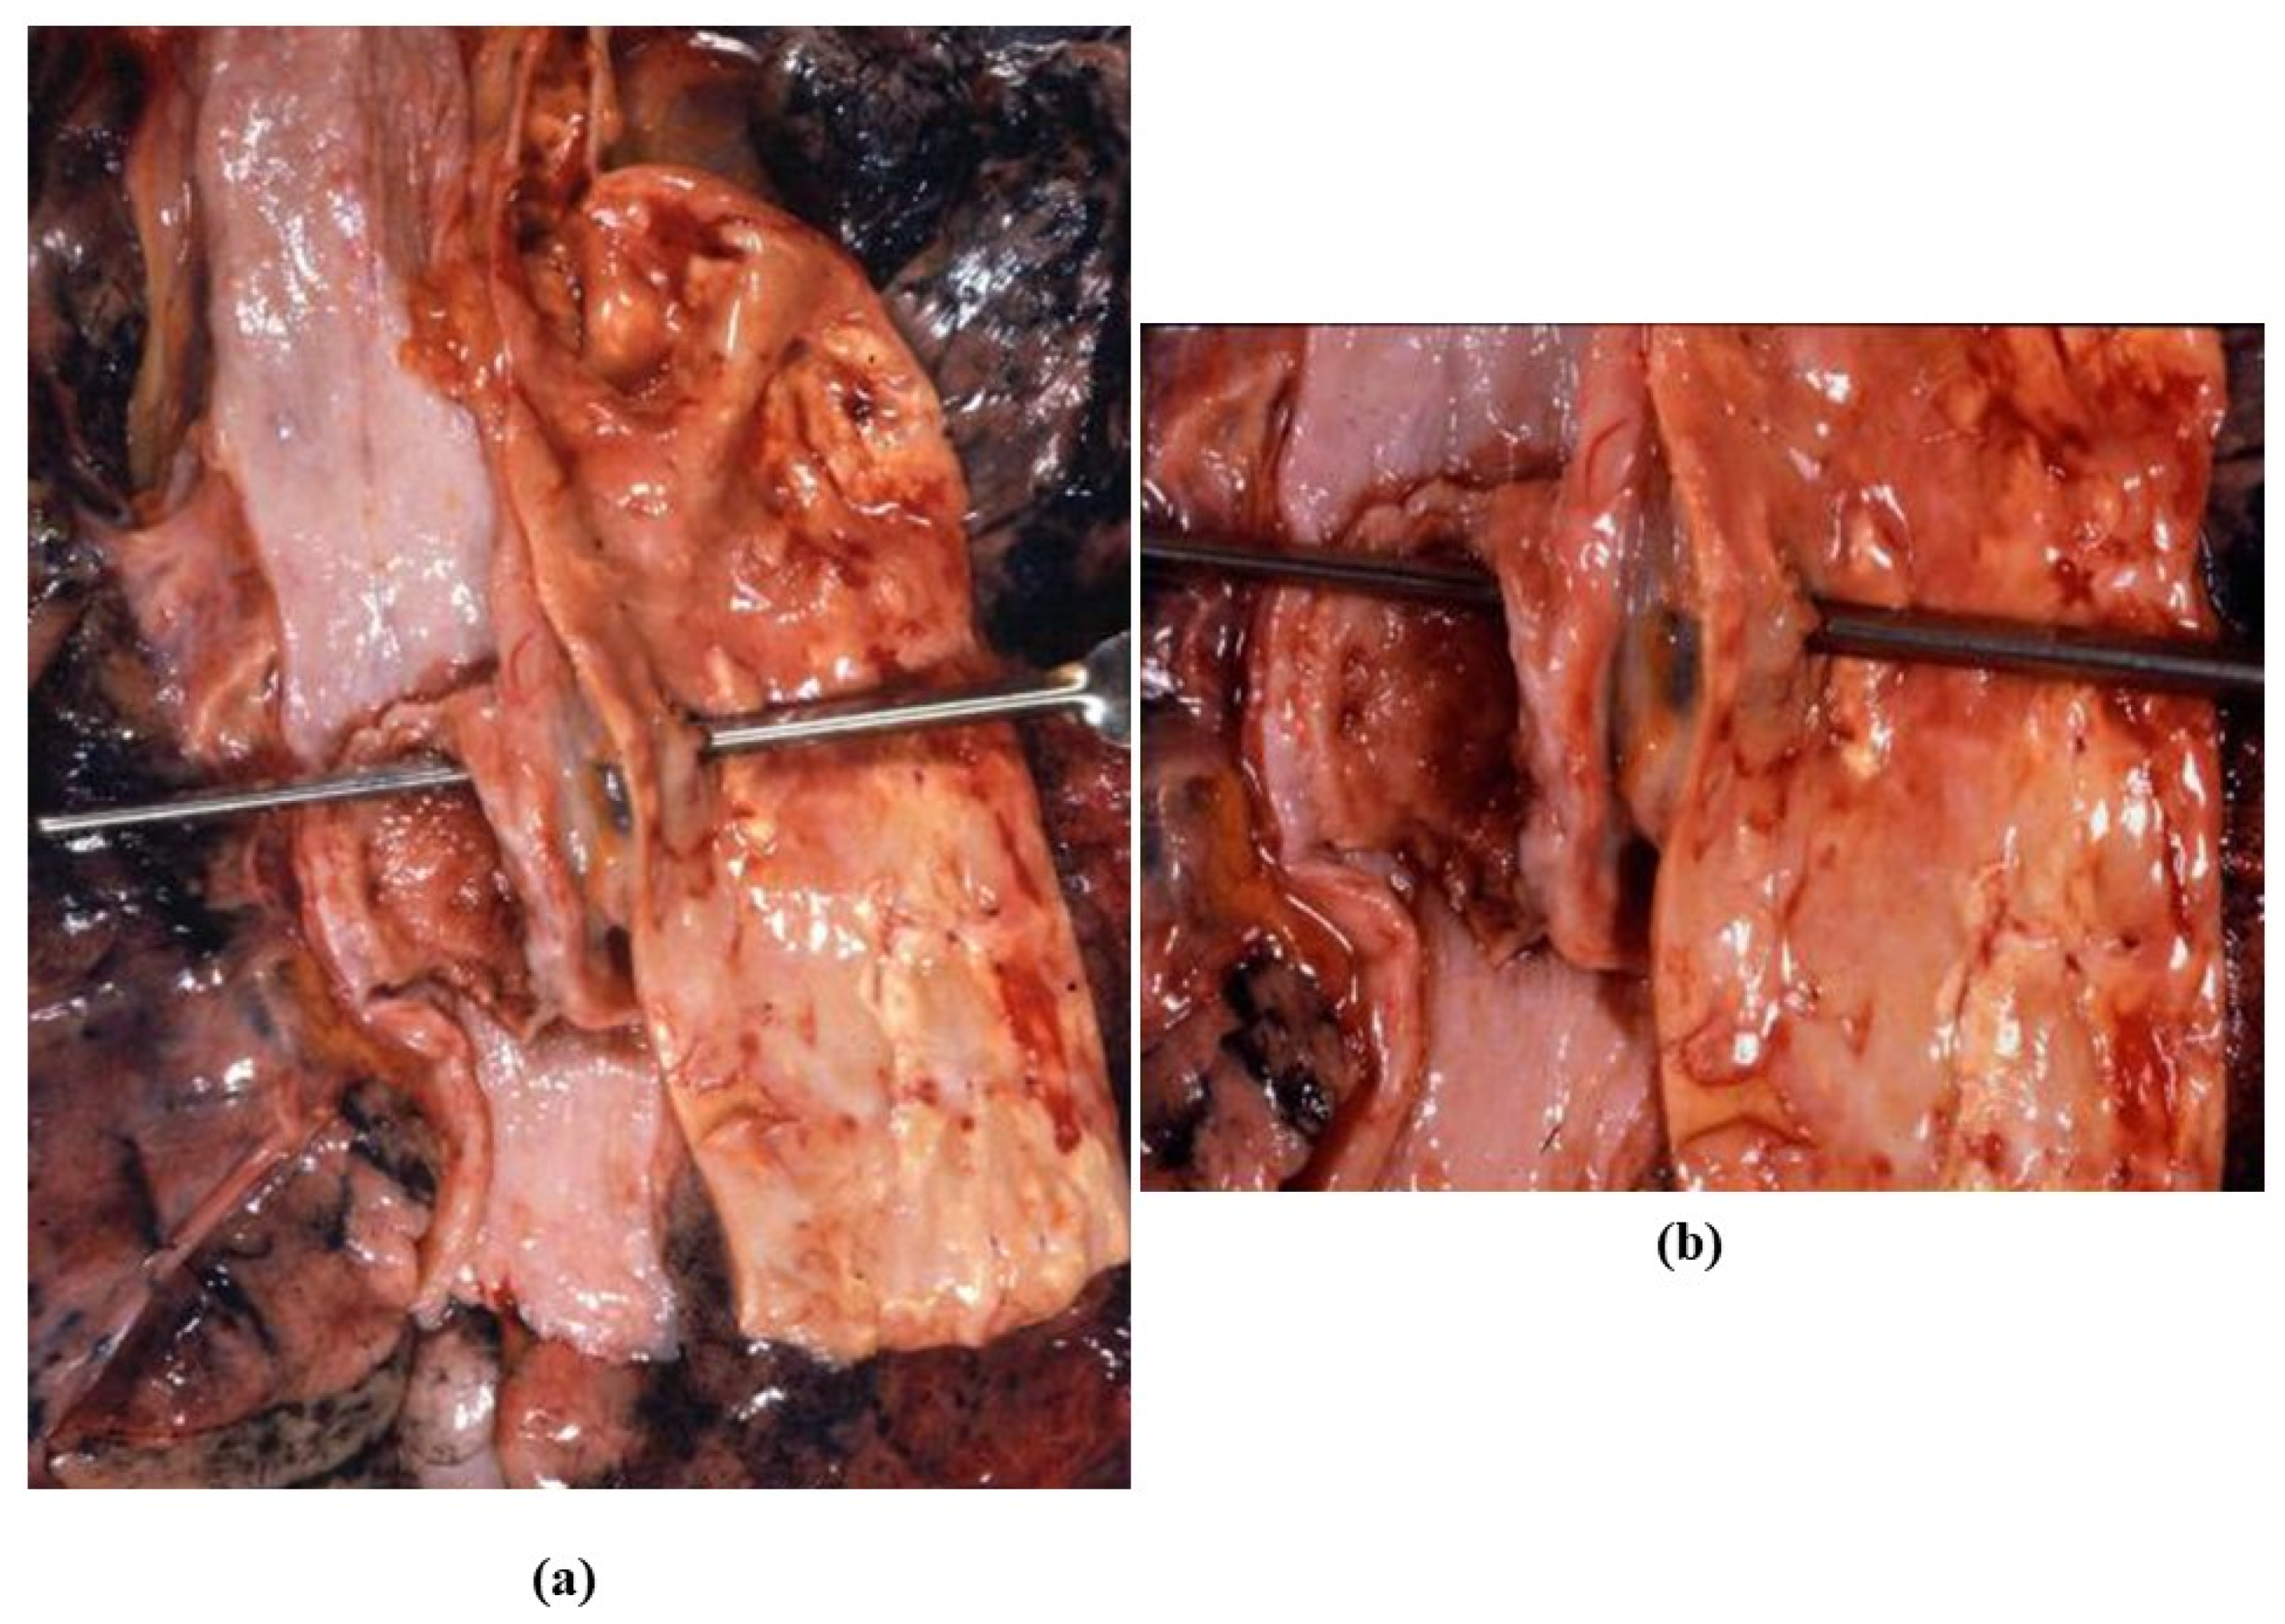

3.4. Inflammatory Diseases of the Aorta